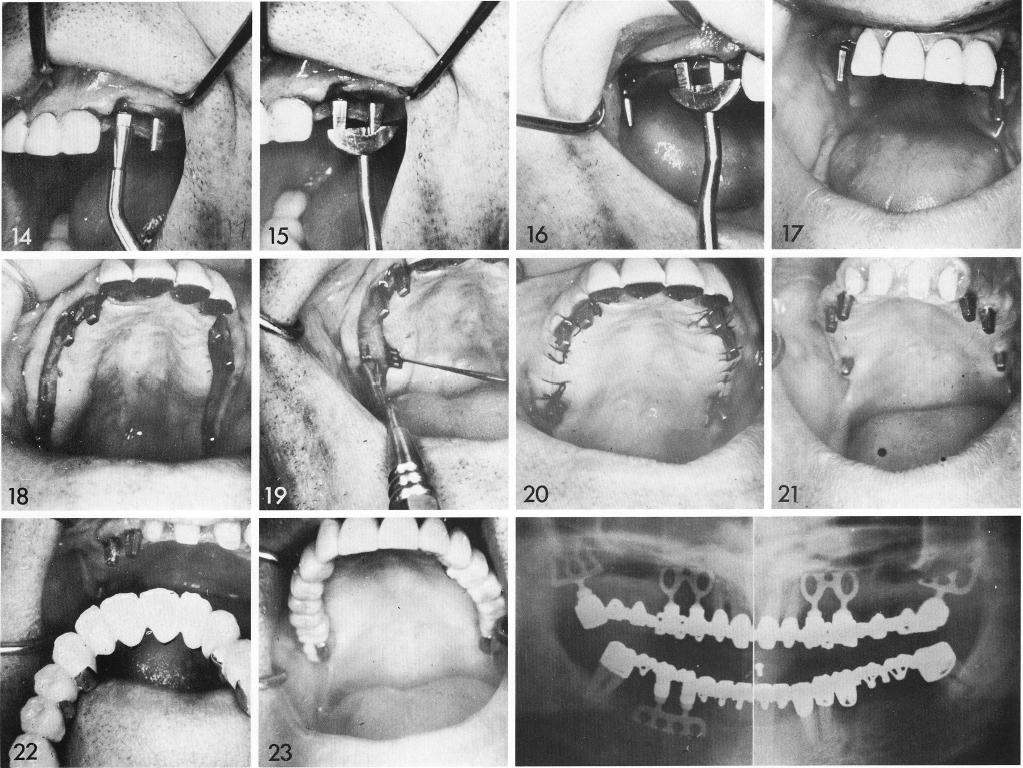

The photographic sequence in this case is excellent. The patient's problem was bilaterally edentulous posterior free-end areas (1,2). Upon exposure of the ridge (3), the bone appears wide enough—and the radiographs con-firm deep enough—for bladevents. First the channels are made (4). The left open-socket bladevent is matched to its channel (5), and bent into a curve (6) until it fits passively (7). It is left lodged there while the tuberosity blade-vent is tried (8). Bilaterally the procedure is repeated (9,10). Then one by one the bladevents are removed and the necks of the posts bent (11) until all posts are parallel with each other and the natural abutments (12). Then the bladevents are sunk home (13-15), sometimes with a little additional force applied to the more mesial post in the harder bone near the teeth (14). When all bladevents are properly seated (16-19), with the bottoms of the posts touching the crest, the tissues are sutured closed (20). A temporary appliance is used until the tissues heal (21), and then the final restoration is fabricated and inserted (22,23).

1 All maxillary bladevent implants are properly seated